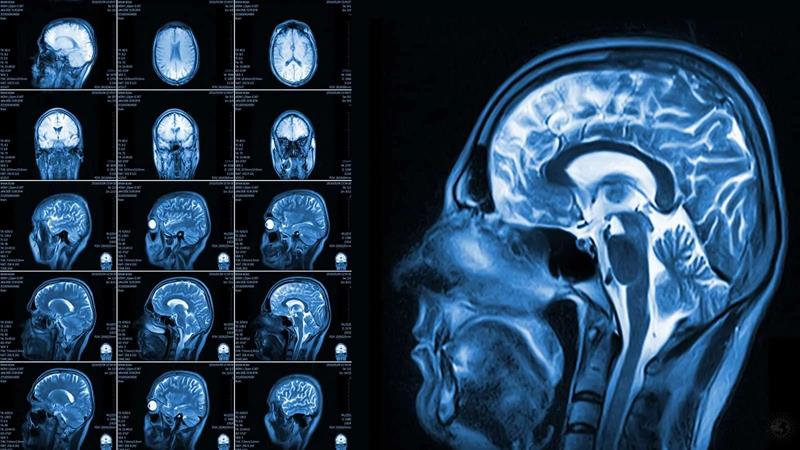

El principal atributo del efecto de la música en nuestro cerebro es que estimula múltiples áreas de nuestro cerebro. Nuestro cerebro responde en regiones que incluyen: escucha, emociones, recuerdos, movimiento físico e imágenes visuales.